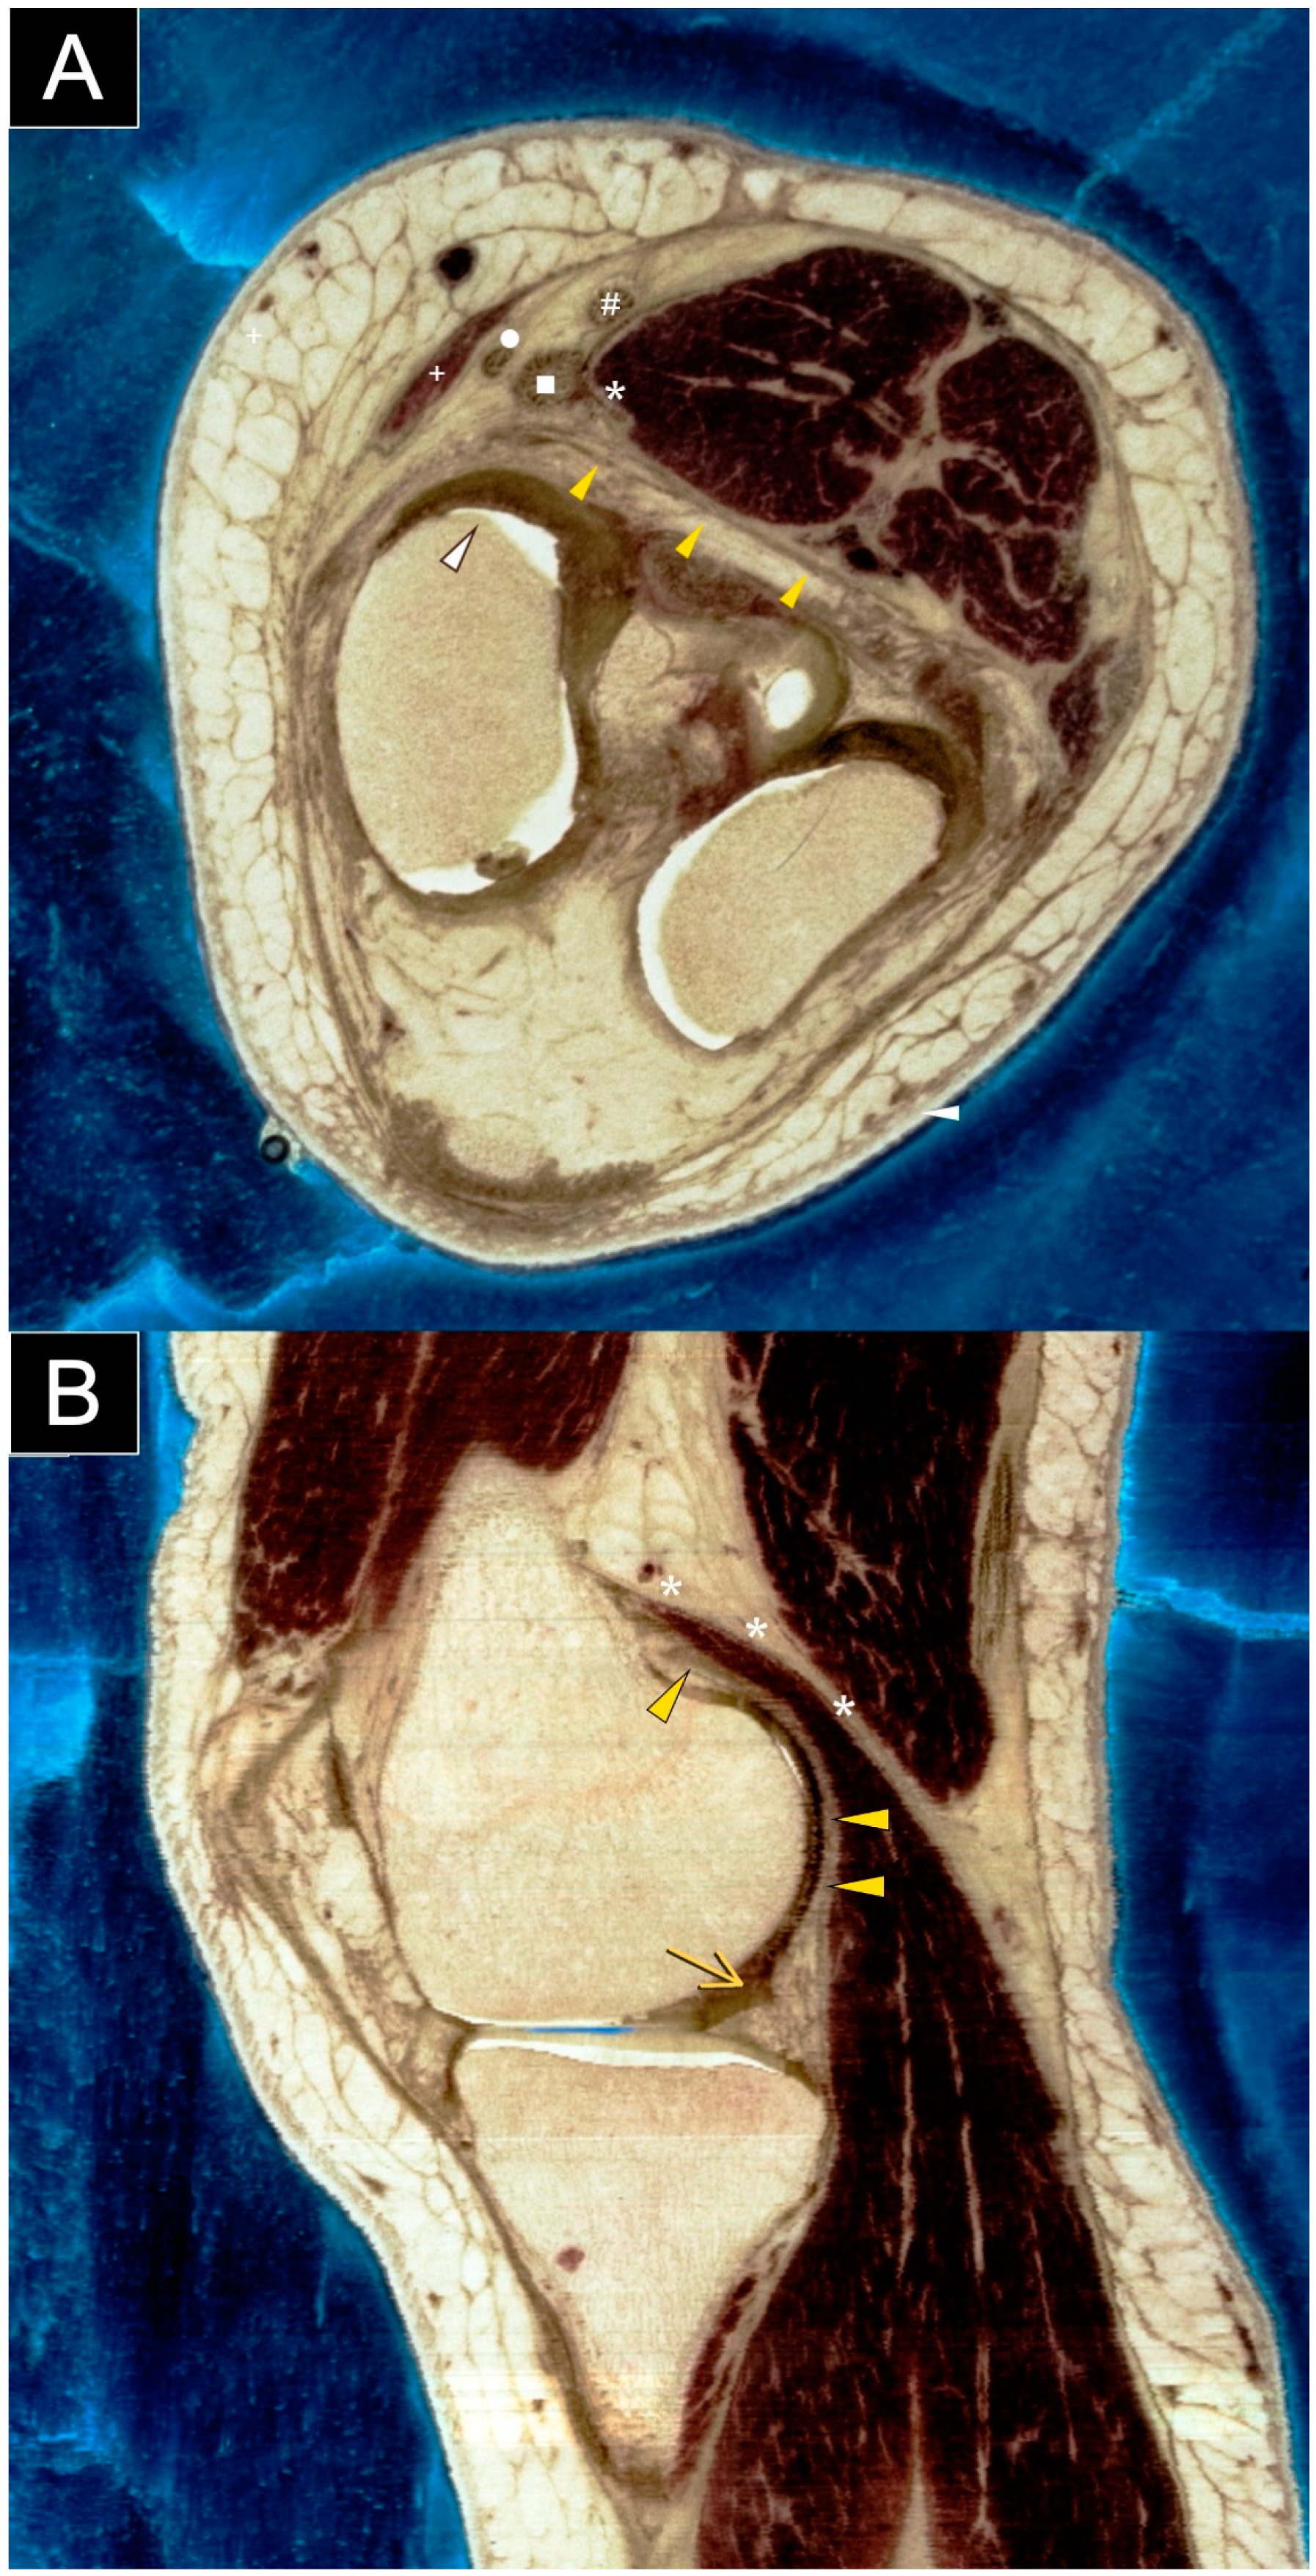

Figure 7. Axial (A) and sagittal (B) sections of a cadaveric knee specimen illustrate the structures located at or adjacent to the posteromedial knee capsule. Understanding the normal anatomy of the posteromedial knee is essential for evaluating and managing cases involving suspected cement extrusion following knee replacement surgery. The labeled structures include the posterior capsule (yellow arrowhead), posterior femoral condyle (white arrowhead), posterior horn of the medial meniscus (yellow arrow), medial head of the gastrocnemius (asterisk), semimembranosus tendon (square), gracilis tendon (circle), semitendinosus tendon (hash sign), and sartorius tendon (plus sign). Images are courtesy of the Visible Human Project® of the National Library of Medicine. This article highlights cement extrusion following knee replacement, a phenomenon reported in the literature. A PubMed search using the keywords ‘knee replacement’, ‘cement’, and ’extrusion’ identified several reports. Otani et al. [2] described a 57-year-old patient with rheumatoid arthritis who developed posterolateral impingement after total knee arthroplasty. Radiographs revealed bone cement extruding posterolaterally to the tibial tray. Arthrotomy via a posterolateral approach showed that impingement was caused not only by cement extrusion against the fibular head but also by proximal tibiofibular joint instability. Palco et al. [3] and Kim et al. [4] reported cases of bone cement fragments causing mechanical symptoms after medial uni-compartmental knee replacement. Radiographs were obtained, and arthroscopic removal of the loose cement bodies resulted in positive outcomes. To our knowledge, this is the first report to highlight the unique role of ultrasound in detailing the anatomy of extruded cement and adjacent soft tissues after knee replacement surgery. Ultrasound is particularly valuable for assessing soft tissues around metallic implants, offering both anatomical and functional insights. This modality allows clinicians to evaluate and monitor soft tissue structures adjacent to metallic implants, guiding treatment strategies and potentially improving patient outcomes. However, while our article highlighted the usefulness and portability of ultrasound imaging in evaluating post-arthroplasty knee complications, its application is limited to a single case. Therefore, we have included a SWOT analysis (Material S1 in the Supplemental Materials) to support the broader application of ultrasound in the general population.